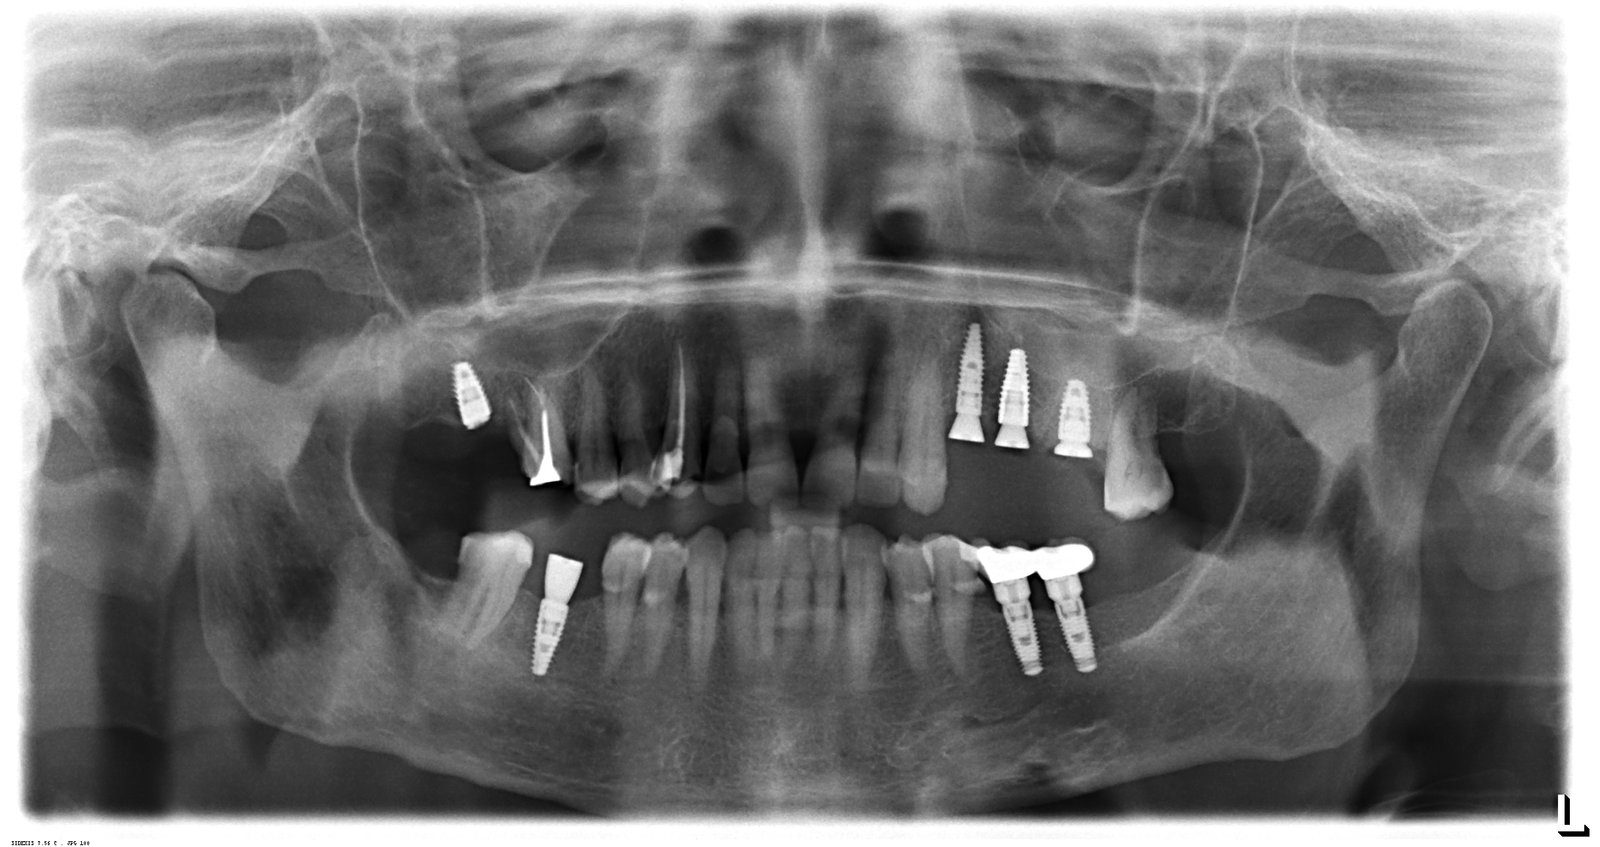

Saludos estimados colegas, les comparto este caso para que me puedan ayudar a resolver una incertidumbre de la marca de estos implantes. Paciente femenina que acude a nuestra consulta [...]